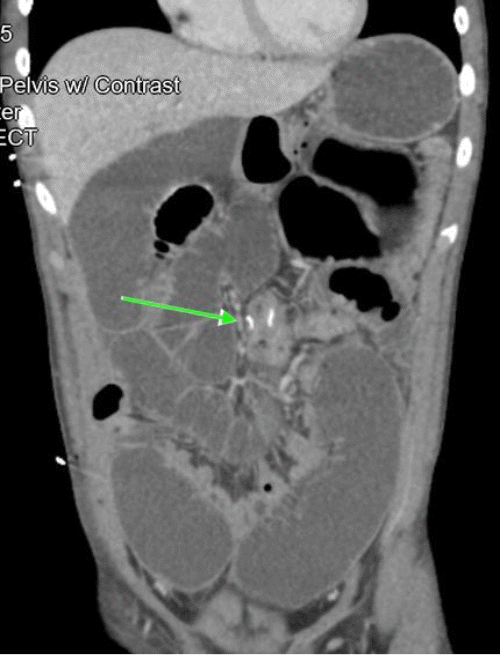

A 16-year-old male with no significant past medical or surgical history presented to the emergency department as a tier 1 trauma activation following a gunshot wound to the right lower abdomen. Primary survey revealed patent airway, normal breathing, palpable peripheral pulses, and stable vital signs. A 1 cm circular penetrating wound in the right lower quadrant was observed with minimal blood oozing. Abdominal examination revealed diffuse tenderness, distention, rigidity, and guarding. Physical exam and bedside focused assessment with sonography (FAST) were otherwise unremarkable. Upright chest and abdominal radiographs demonstrated free air under the diaphragm (Figure 1). The patient was urgently taken to the operating room for exploratory laparotomy.

Figure 1. Radiographic Evidence of Pneumoperitoneum Following Penetrating Abdominal Trauma. Published with Permission

(A) Upright chest radiograph and (B) abdominal radiograph demonstrating free air under the diaphragm, consistent with pneumoperitoneum